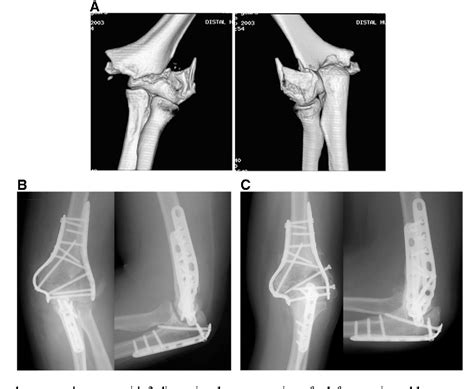

Trauma: Comminuted transcondylar distal humerus fracture

Trauma: Comminuted transcondylar distal humerus fracture from www.eatonhand.com

Conclusions transcondylar fractures are the most common type of extra‐articular bicolumnar fracture and may be more common than previously recognized. The fracture involves the cortex circumferentially and there may be displacement. Transcondylar fractures of the distal humerus have characteristic transverse, anterior shear, or posterior shear fracture patterns. Tietjen}, journal={the journal of bone and joint surgery. Transcondylar humerus fracture in pediatric age. Transcondylar — across or through the condyles; The fracture is usually transverse or oblique and above the medial and lateral condyles and epicondyles. Musculoskeletal trauma (second coronal reformat nect from the same patient confirms transcondylar course of fracture. A supracondylar humerus fracture is a fracture of the distal humerus just above the elbow joint. What does transcondylar fracture mean? This fracture pattern is relatively rare in. Specific coding for transcondylar fracture of humerus. Make an appointment to get a consultation right now! Open transcondylar femoral fracture iiib: To code a diagnosis of this type, you must use one of the six child codes of s42.47 that describes the diagnosis 'transcondylar fracture of humerus' in more detail. Stabilization of this fracture is often difficult because the distal fragments are small. Problems like these can only be correctly handled by y.